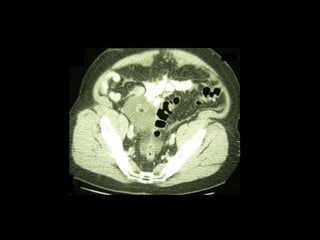

Pseudomyxoma peritonei (PMP) is a rare condition characterized by gelatinous ascites resulting from the rupture of appendiceal mucinous tumors, leading to significant abdominal complications. The incidence is approximately 2 cases per million per year, with a predominance in females, and diagnosis often relies on imaging techniques like ultrasound and CT scans. Effective treatment involves cytoreductive surgery combined with hyperthermic intraperitoneal chemotherapy (HIPEC) to manage disease progression and improve outcomes.